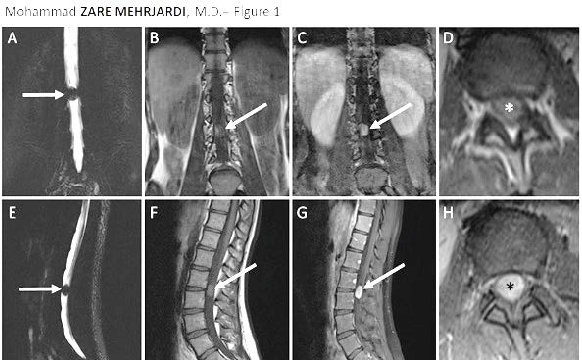

MRI wordt vaak ingezet bij aanhoudende lage-rugklachten vanwege de uitgebreide weergave van weke delen.

MRI kan:

tussenwervelschijven beoordelen

zenuwstructuren visualiseren

bijkomende afwijkingen aantonen

Beperkingen:

botfusies soms minder duidelijk zichtbaar

geen directe relatie tussen bevinding en pijn aantoonbaar

Afwijkingen op MRI zijn niet automatisch de oorzaak van klachten. Klinische correlatie blijft noodzakelijk.

Een belangrijk aandachtspunt bij LSTV’s is correcte nummering van de wervelkolom.

Door overgangsvariaties kan:

L5 worden aangezien voor S1

verwarring ontstaan over het exacte niveau

interpretatie van beeldvorming worden bemoeilijkt

Onjuiste nummering kan gevolgen hebben voor verdere diagnostiek en behandeling. Zorgvuldige beoordeling is daarom essentieel.